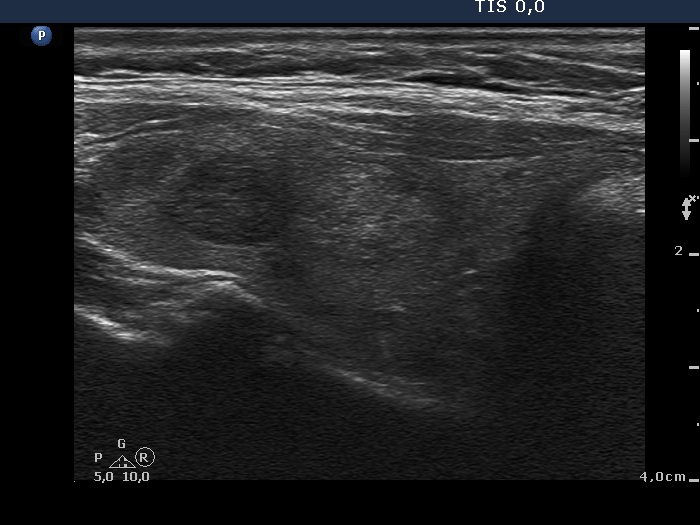

Study on 100 consecutive patients with thyroid nodule - case 066 (ultrasonographic picture 10)

Left lobe, another longitudinal scan.